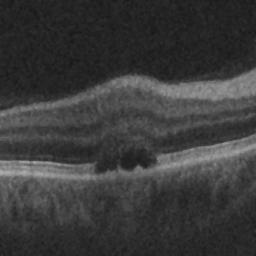

The qualitative results of the proposed system is shown in the Fig. 3. The detection task is evaluated using Area Under the Curve(AUC) metric and the segmentation task is evaluated using Dice Coefficient(DC) metric and the results are presented in Table1

| (a) De-noised OCT slice | (b)Predicted fluid region | (c)Manual fluid segmentation |

| (d) De-noised OCT slice | (e)Predicted fluid region | (f)Manual fluid segmentation |

| (g) De-noised OCT slice | (h)Predicted fluid region | (i)Manual fluid segmentation |

| (j) De-noised OCT slice | (k)Predicted fluid region | (l)Manual fluid segmentation |

| (m) De-noised OCT slice | (n)Predicted fluid region | (o)Manual fluid segmentation |